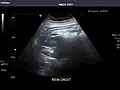

Liver

Ultrasonography of the liver with some standard measurements[6]

In patients with deranged liver function tests, ultrasound may show increased liver size (hepatomegaly), increased reflectiveness (which might, for example, indicate cholestasis), gallbladder or bile duct diseases, or a tumor in the liver.

Ultrasonography of liver tumors involves two stages: detection and characterization. Tumor detection is based on the performance of the method and should include morphometric information (three axes dimensions, volume) and topographic information (number, location specifying liver segment and lobe/lobes). The specification of these data is important for staging liver tumors and prognosis. Tumor characterization is a complex process based on a sum of criteria leading towards tumor nature definition. Often, other diagnostic procedures, especially interventional ones, are no longer necessary. Tumor characterization using the ultrasound method will be based on the following elements: consistency (solid, liquid, mixed), echogenicity, structure appearance (homogeneous or heterogeneous), delineation from adjacent liver parenchyma (capsular, imprecise), elasticity, posterior acoustic enhancement effect, the relation with neighboring organs or structures (displacement, invasion), vasculature (presence and characteristics on Doppler ultrasonography and contrast-enhanced ultrasound (CEUS).